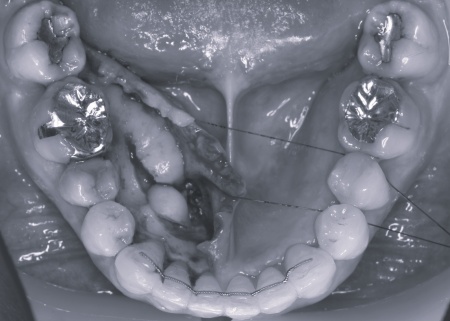

右上下の奥歯に対して、レントゲン撮影と歯間の溝の深さを測る歯周ポケット検査をしたところ、重度の歯周病が認められました。歯を支える骨が大幅に失われ、歯がぐらぐらしている状態です。

また左上下の奥歯についても同様で、重度の歯周病が進行しています。

さらに、下顎の内側には下顎隆起(かがくりゅうき)という骨の出っ張りが見られました。

これは、強く噛む力が長期間かかることで骨が発達して発生するものなので、奥歯への過度な負担を示しています。

続いて上下左右の奥歯に対して、失われた歯を支える骨や歯根膜(歯を支える薄い膜)を再生させるため、骨の再生を促す材料などを充填する歯周組織再生療法を実施しました。

歯周組織再生療法を行いました。